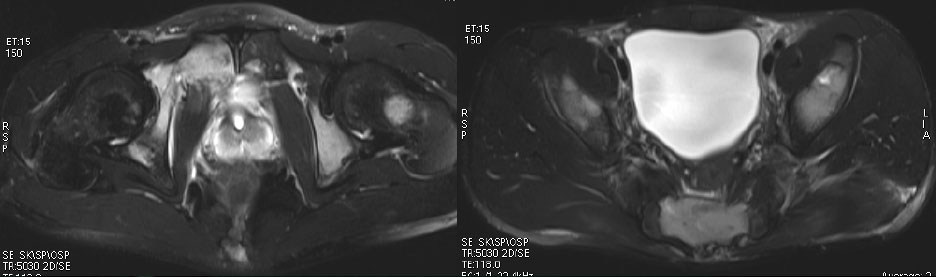

男性,20岁。

颈部疼痛2月,腰部臀部疼痛1月。

前臂肿物活检,病理报告:小圆细胞恶性肿瘤,免疫组化考虑为PNET/尤文氏肉瘤

In pPNET patients with tumors originating from soft tissues, the tumors often demonstrated ill-defined,soft tissue masses and exhibited aggressive spreading to the neighboring tissue.

On T1WI, the tumor demonstrated isointensity or slightly hypointensity; on T2WI, the tumor demonstrated heterogeneous hyperintensity.

The tumor demonstrated heterogeneous enhancement on contrast-enhanced CT/T1WI.

Cystic necrotic component and haemorrhagic change are usually obvious.